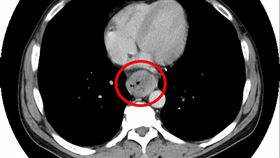

術後半年狂咳不止!竟是他喉嚨長鬍子

高雄一名60多歲的男子先前因罹患下咽癌第4期,經診斷...